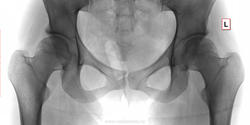

Девушка 1990 года рождения, жалобы на боли в левом тазобедренном суставе около двух месяцев.

Патологических изменений не нахожу.

Расщепление задних дуг позвонков крестца (spina bifida posterior)

Фигуры слезы лево-право несимметричны: слева уже, справа шире. Едва заметная дополнительная тень в области дна вертлужной впадины, выступающая внутрь тазового кольца слева. Итого - признаки прогибания дна вертлуной впадины, возможно, как результат остеомаляции после беременности и родов. Ничего страшного нет; шорты, футболку - и под солнце.

Вижу изменения крестца и правой бедреной кости. Предполагаю, связаны с лучевым лечением заболевания малого таза. Простит меня пациентка, если ошибаюсь.

На МРТ асептический некроз головок обеих бедренных костей 2 стадии. Осложнение химиотерапии по поводу лимфомы.

На рентгеновских снимках норма, на МРТ ненорма. Каждый метод имеет свой предел.

- Вдавленность верхне-наружного головочного контура значит, не совсем уже норма.

По рентгеновским снимкам я бы норму написал.